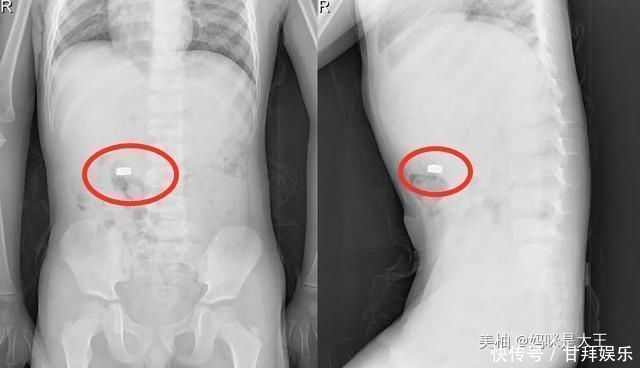

通过医生的检查,发现孩子的肚子里面确实有一颗纽扣大小的电池,还好王女士立即带孩子来了医院,孩子有惊无险。